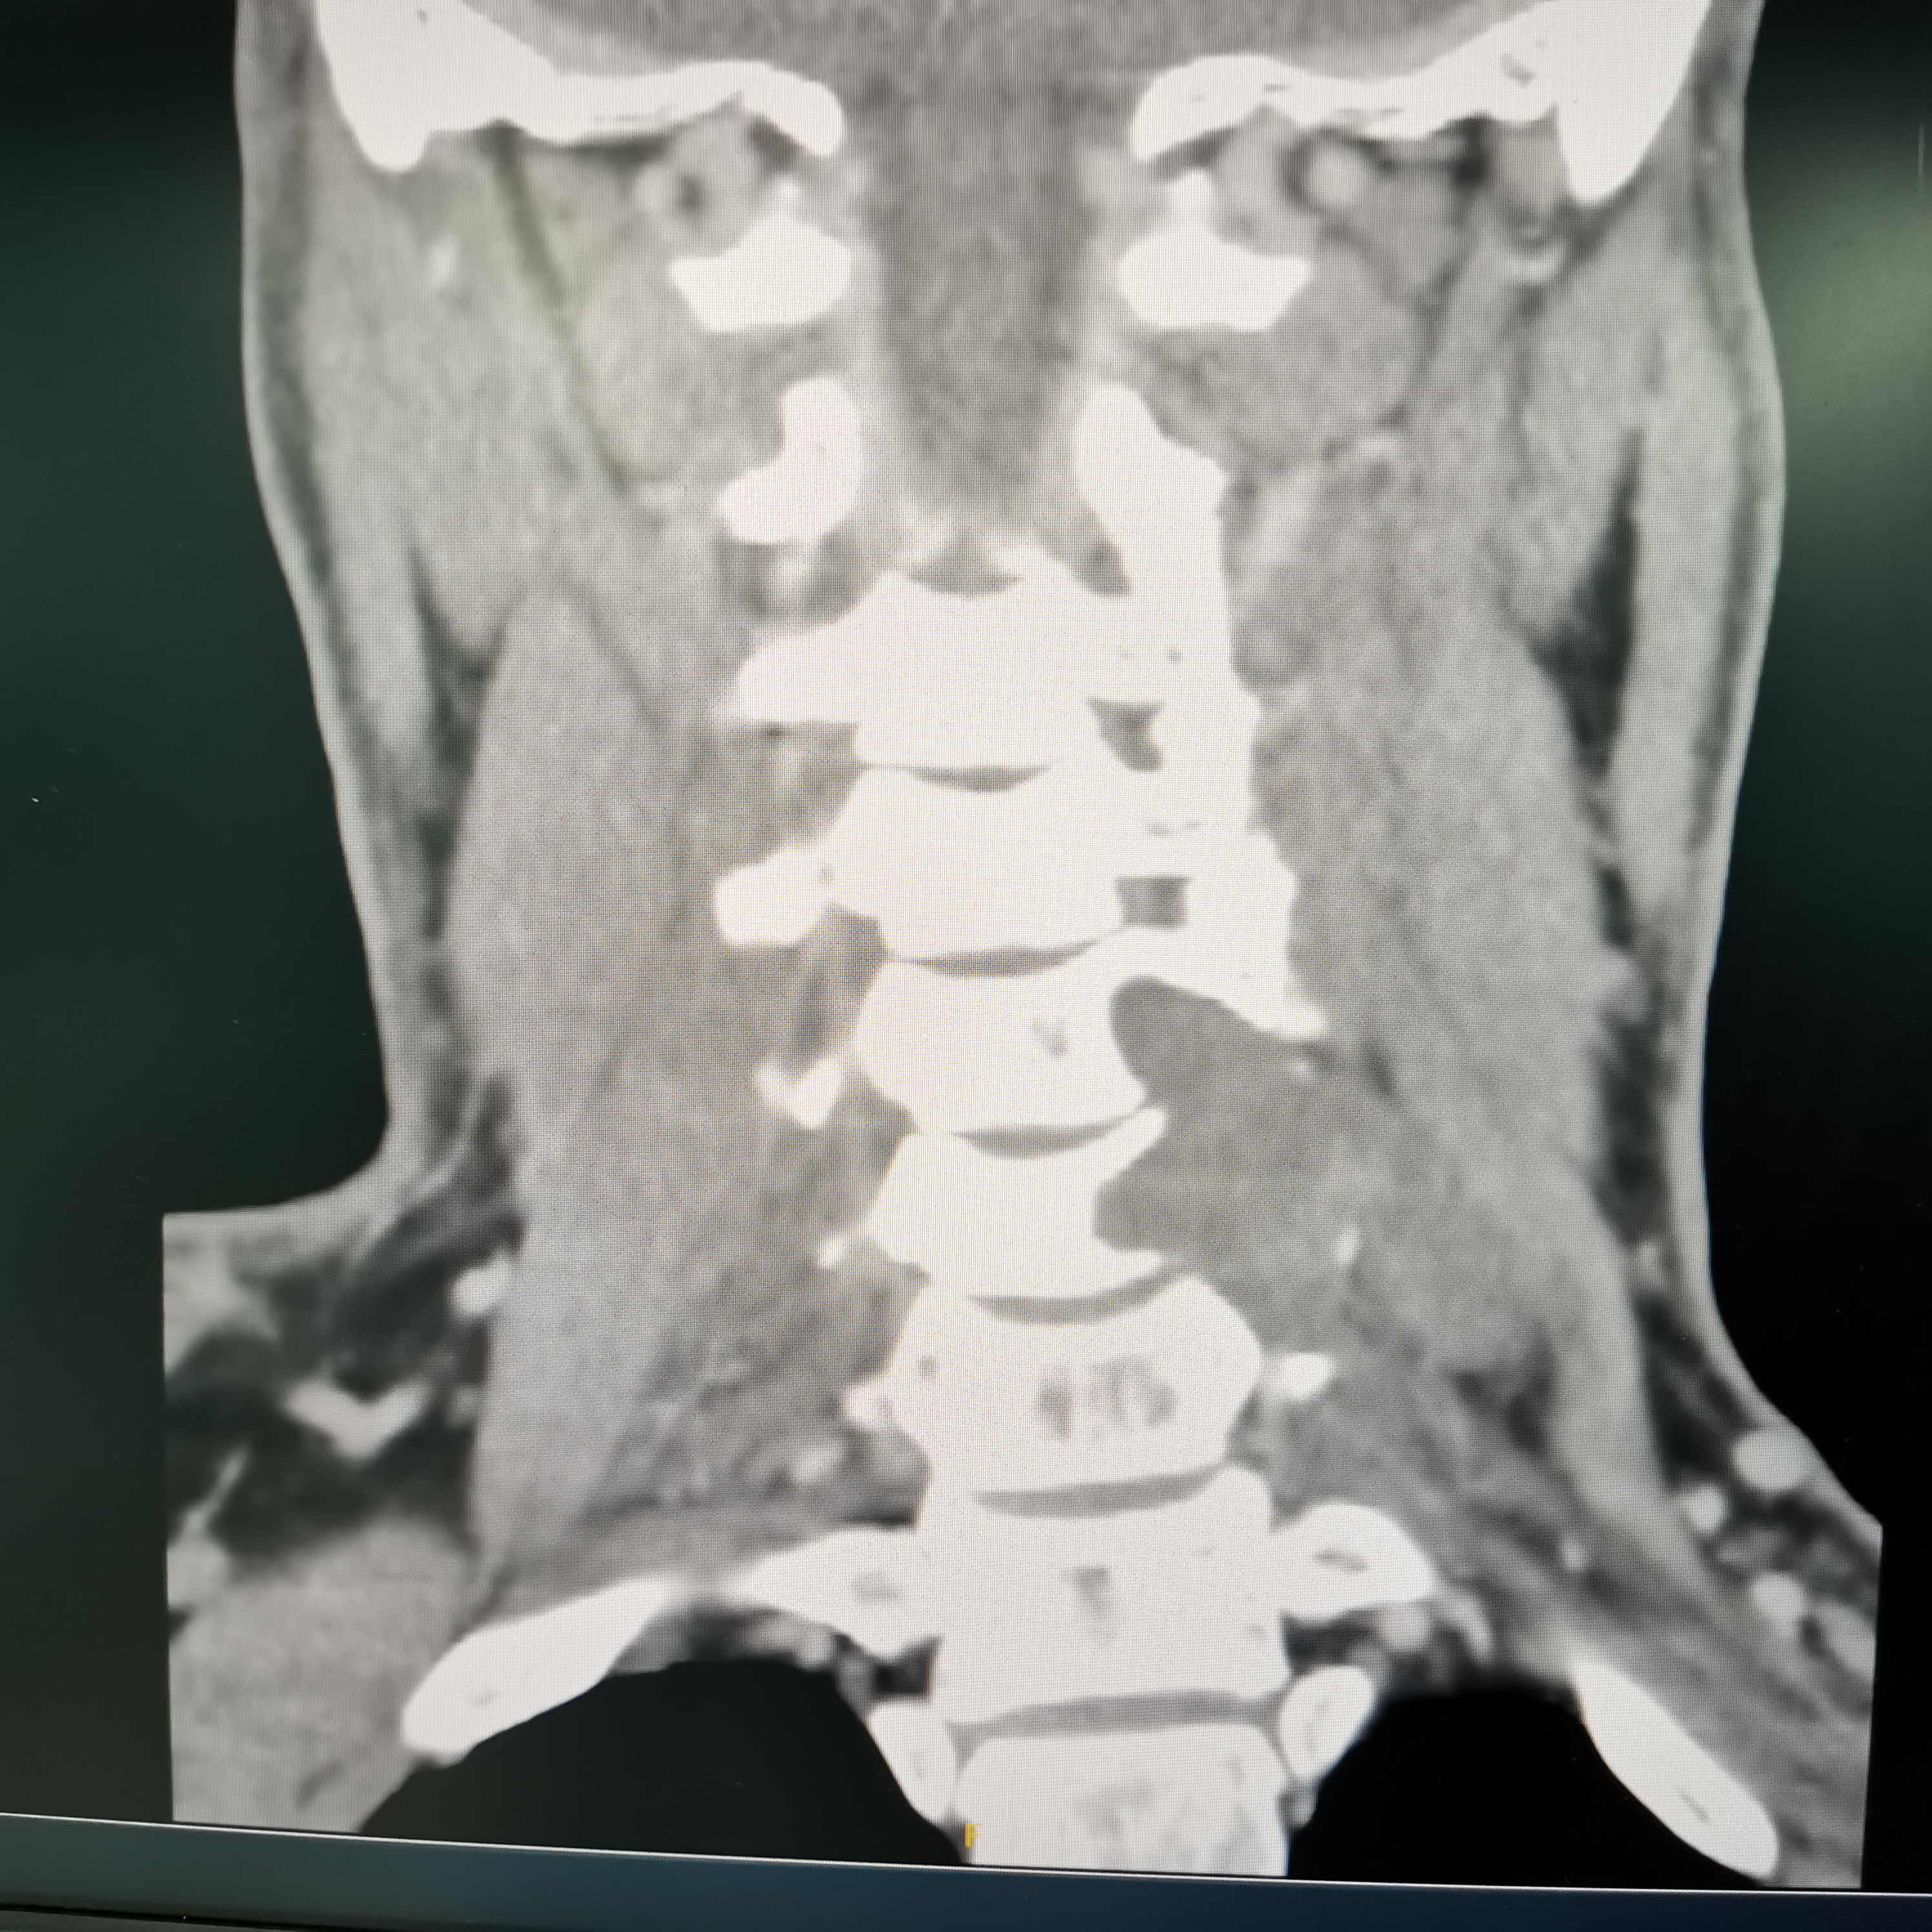

颈椎哑铃型神经纤维瘤,椎间孔汇合,安全又便于操作~